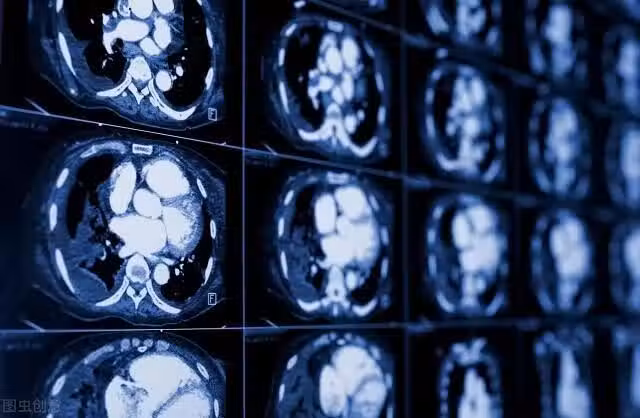

肺癌早期最常見的症狀是咳嗽,但由於咳嗽可能是很多原因引起的,比如感冒、支氣管炎等,所以很容易被忽視或當做其他的疾病對待。

根據美國癌症協會(ACS)的研究,單側眼皮下垂或無力可能源自一種罕見的肺癌,臨床上通常被稱為肺上溝癌或肺尖癌。這種類型的腫瘤位於肺的一側頂部,也就是我們所說的肺的頂端部分,隨著腫瘤的生長,它經常會擴散到神經、胸廓、血管、淋巴結和上椎骨。

這個位置的肺癌往往會影響連接大腦、眼睛和臉部的神經通路,引發一系列被稱為霍納綜合徵(Horner Syndrome)的症狀。除了單眼皮下垂外,患者患眼的瞳孔通常較小,患側面部出汗很少或不出汗。